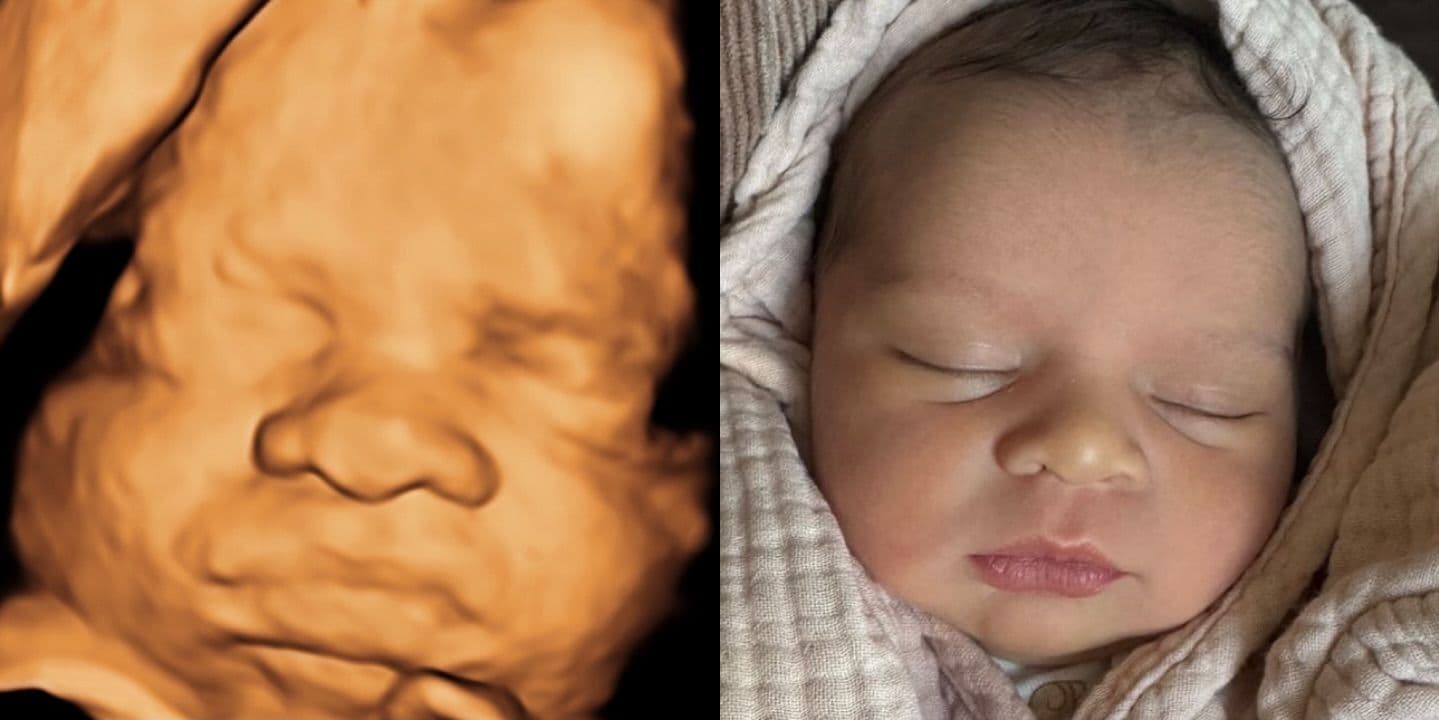

What Parents Actually Experience

The most common reaction after birth? "The nose looks nothing like the ultrasound." Pregnancy forums are full of parents sharing their 3D ultrasound next to their newborn photo, and the difference is striking. Wide, flat ultrasound noses turn into perfectly normal (often tiny) baby noses.

Ultrasound studios publish before-and-after galleries showing 3D scans alongside the born baby—and you can see the pattern clearly: the nose is almost always wider on the scan. Browse real examples at Fetal Vision Imaging, 3D Baby Boutique, and Baby Moments Ultrasound. Not every case is dramatic—some noses match closely—but the wide-nose effect is by far the most common outcome.

This makes sense when you understand what a 3D ultrasound actually is: a surface rendering built from sound waves, not a photograph. It captures general shape but distorts proportions, especially for protruding features like the nose.